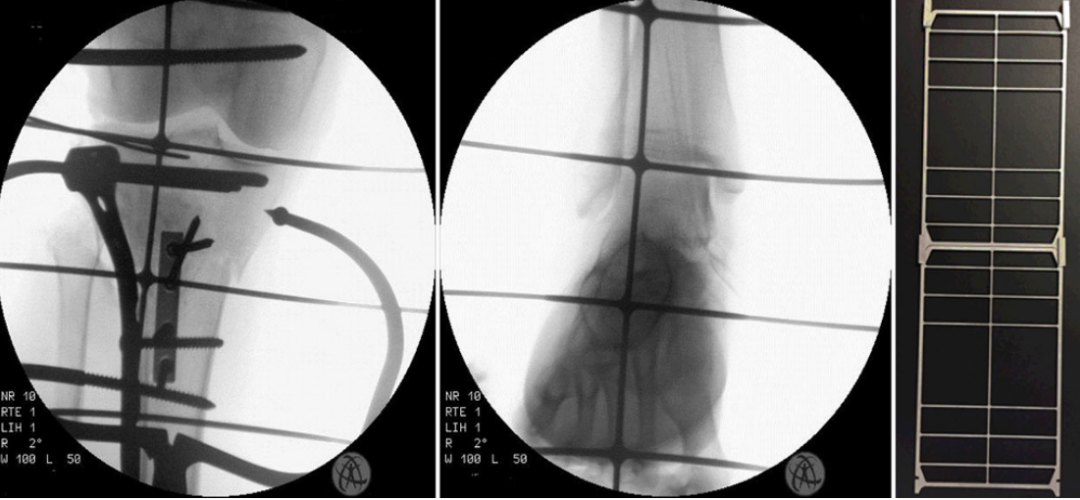

伸展型骨折中,胫骨结节可能发生骨性分离,需针对性复位固定以中和伸肌牵拉力并恢复伸膝装置功能(图6)。

图6:3.5/2.7毫米复位钢板可作为“单向复位钳”(unidimensional repositioning forceps),既不会影响必要的支撑钢板定位(板叠板概念,Pate-on-plate concept),也可用于中和髌腱止点骨折部位的拉力。